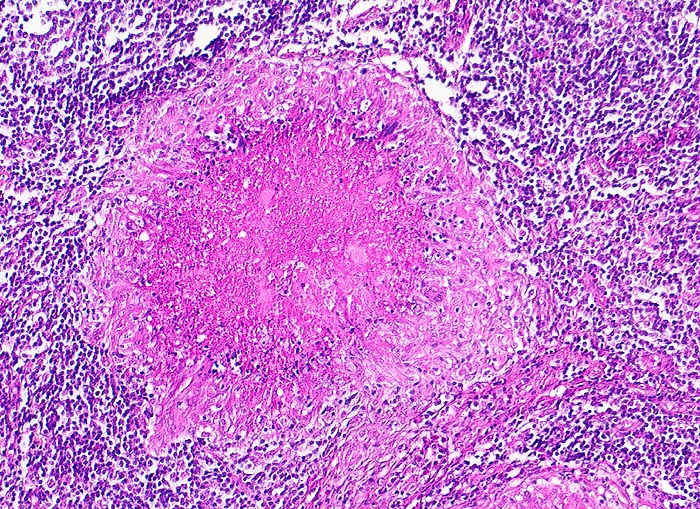

Lymphknotentuberkulose: verkäsendes Granulom

Granulom mit zentraler hypereosinophiler verkäsender Nekrose. Heller Randsaum aus Epitheloidzellen.

Konglomerattumor am Hals mit Fistelbildung bei Patient aus Zimbabwe.

Verkäste Granulome treten bei herabgesetzter Resistenz des Organismus auf (exsudative Tuberkulose). Je ausgeprägter die Verkäsung und je geringer die Epitheloidzellreaktion, desto schlechter die Abwehrlage. Im schlimmsten Fall (bei der Tuberculosepsis Landouzy) sind nur noch reaktionslose Nekrosen zu beobachten. Bei guter Abwehrlage fehlt die Verkäsung und es liegen reine Epitheloidzelltuberkel (produktive Tuberkulose) wie bei einer Sarkoidose vor.